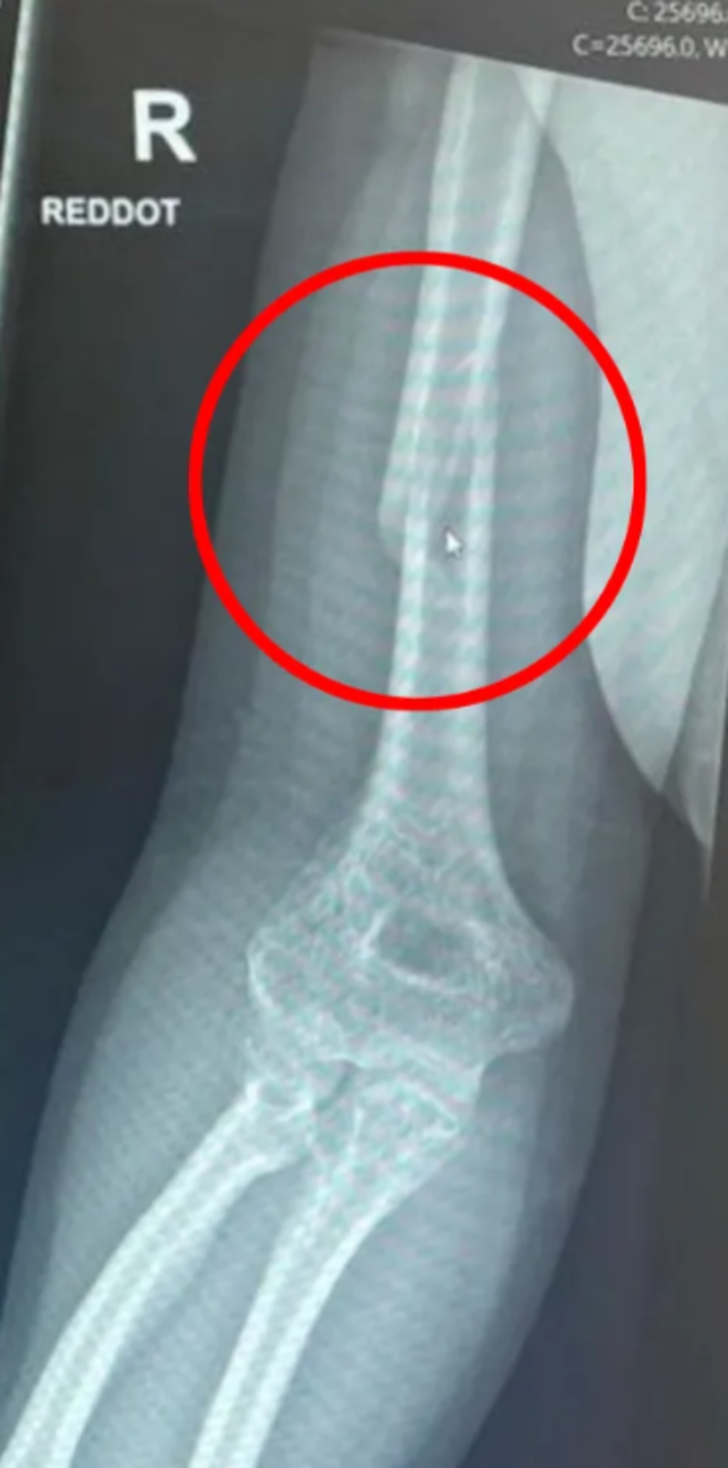

Sosyal medyada bir partide tanımadığı bir adama meydan okuyarak bilek güreşi yapmaya karar veren Daisy Johnson isimli bir kadın o anları sosyal medyadan paylaşınca gündem oldu. Genç kadın rekabetin alevlendiği anlarda kolunun kırıldığını söyledi. Hastaneye kaldırılan kadın üst kolunda omuza bağlanan bir kemik olan humerusunda spiral bir kırık yaşadı.